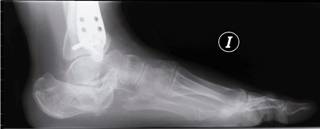

Mala consolidación tipo II: exostosis lateral prominente y artrosis subastragalina (Figura 7). Tratamiento mediante exostectomía lateral, tenólisis de peroneos y artrodesis subastragalina con injerto estructural en bloque (Figuras 8 y 9).

Mala consolidación tipo III: exostosis prominente, artrosis subastragalina y mala alineación del retropié mayor a 10o. Tratamiento mediante exostectomía, tenólisis de peroneos, artrodesis subastragalina con injerto en bloque (artrodesis y distracción), además de osteotomía de calcáneo (varizante o valguizante).